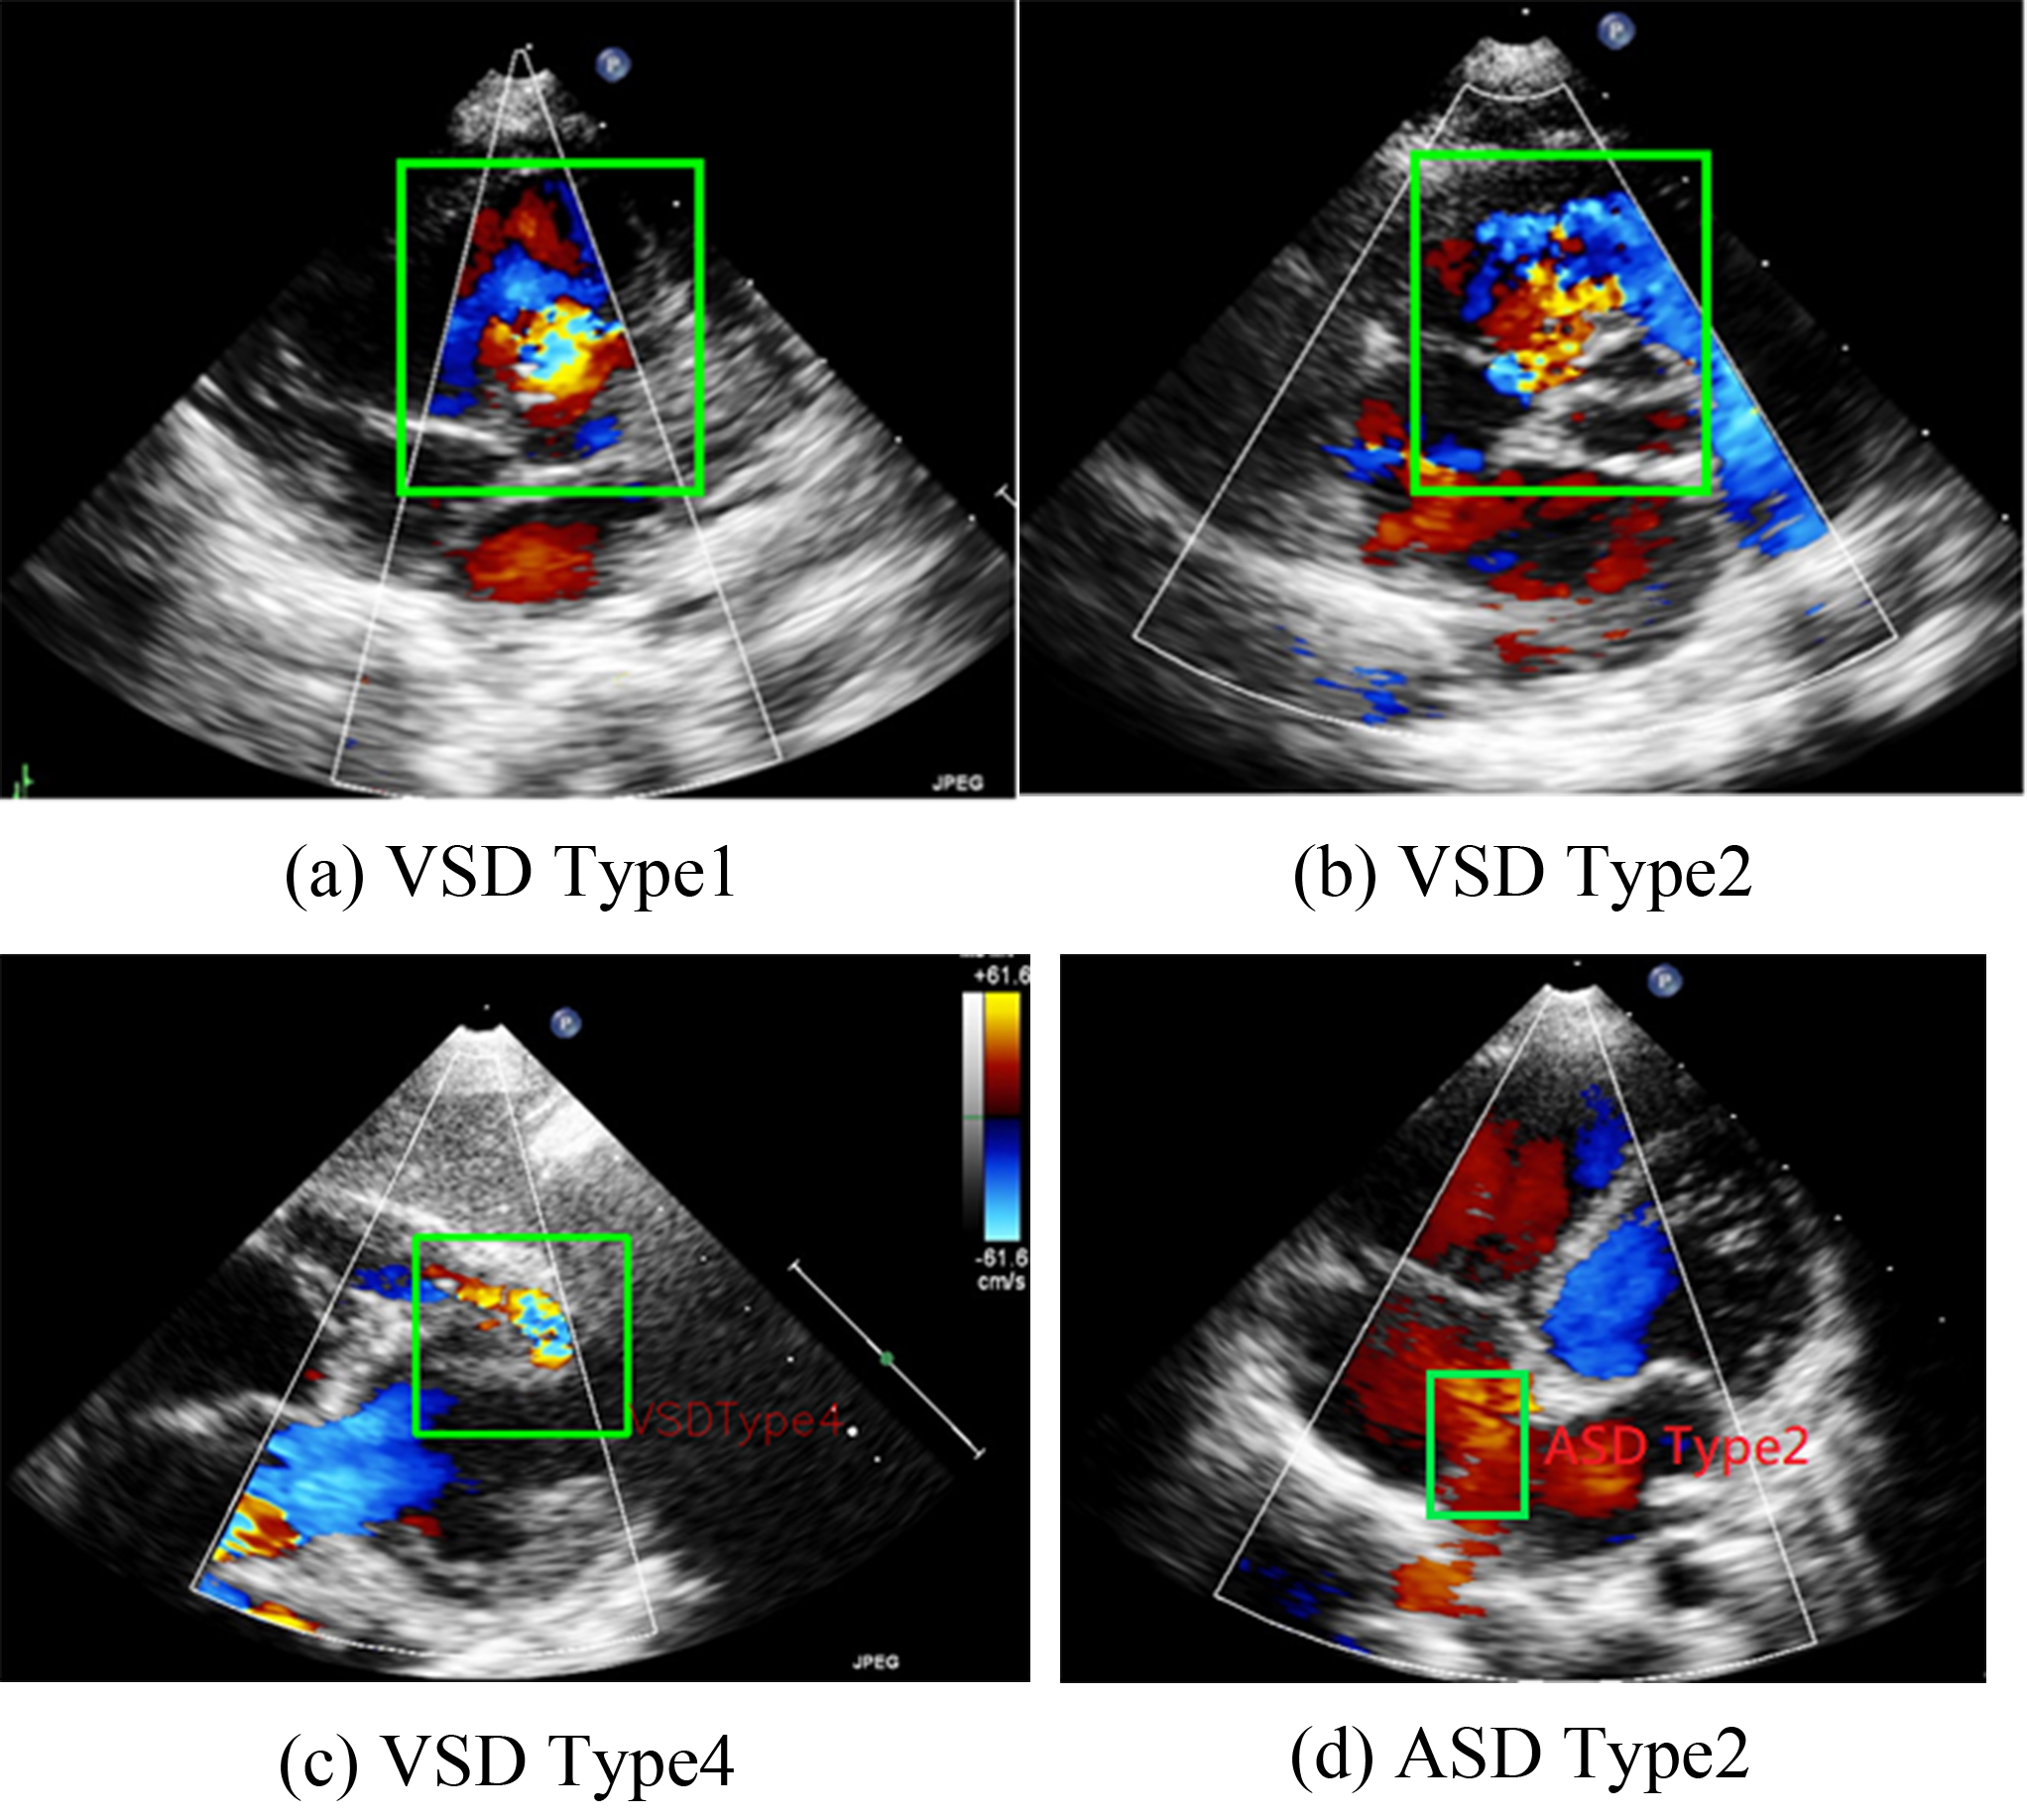

VSD can be categorized into four types on the basis of its location in the right ventricular septum [4]. The present study focuses on Type II VSDs. Type II VSD is a membranous VSD [Fig. 1b] located in the interventricular area of the membranous septum. Membranous VSD is the most common type of VSD, accounting for more than 50% of VSD cases. The recommended interventions for VSD are those outlined in the guidelines proposed by Marelli et al. [1].

Fig. 1.

Representations of various ventricular septal defect (VSD) types and atrial septal defects (ASD) Type 2. (a–c) are the three types of VSD. (d) shows a typical pattern of ASD Type 2.

ASD occurs in the atrial septum. As illustrated in Fig. 1, ASD secundum (or Type II ASD) is the most common ASD type and accounts for approximately 80% of ASD cases. Type II ASD is generally caused by the enlargement of the foramen ovale and the inadequate development of the septum secundum.